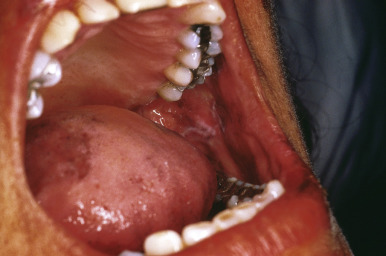

The pigmentation of Addison disease is most intense in the flexures, at sites of pressure and friction, in the creases of the palms and soles ( Fig. 23-6 ), in the nails, in sun-exposed areas, and in normally hyperpigmented areas such as the genitalia and areolae. Pigmentation of the conjunctivae and vaginal mucous membranes is common, and pigmentary changes of the oral mucosae ( Fig. 23-7 ) include spotty or streaked blue-black to brown hyperpigmentation of the gingivae, tongue, hard palate, and buccal mucosa. In addition, increased pigmentation may be noted in existing nevi. The pigmentation may in some children be quite diffuse. Labial pigmentation and longitudinal pigmentary streaks of the fingernails similar to those in Laugier–Hunziker syndrome have been observed. Because the pigmentation may in some cases be subtle, comparison of the patient to other family members may be useful in highlighting the clinical findings. In one series of 18 pediatric patients with primary adrenal insufficiency at one institution, 12 (67%) exhibited cutaneous hyperpigmentation. Primary adrenal insufficiency without hyperpigmentation has been reported and may result in a delay in the diagnosis of Addison disease. Loss of body hair may be another cutaneous finding in this disorder.